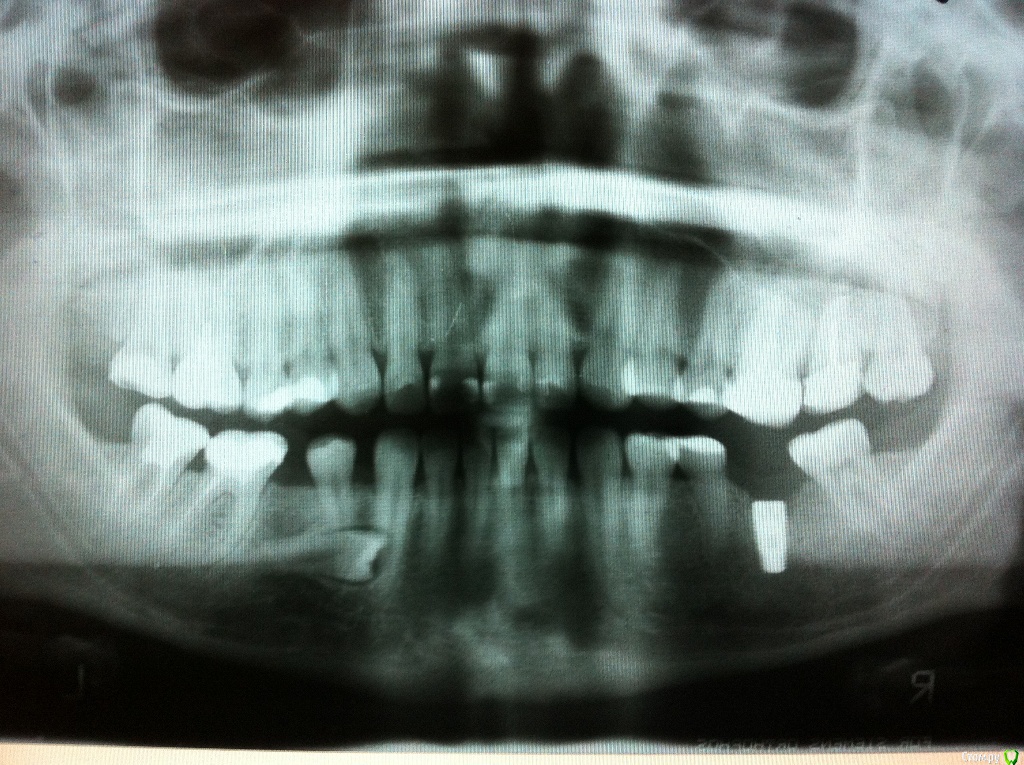

m.gel Опубликовано 27 мая, 2016 Поделиться Опубликовано 27 мая, 2016 Здравствуйте! Обращаюсь к вам за советом, так как живу в небольшом городе, где есть всего один хороший ортодонт (по отзывам). Я была у него на приеме со свей проблемой, но хочется проконсультироваться с другими специалистами. У меня к вам несколько вопросов, очень надеюсь на вашу помощь.1. Дело в том, что у меня долго отсутствовали 2 нижних зуба и верхние противоположные постепенно сместились вниз. Хочу поставить на место отсутствующих нижних зубов импланты, но не знаю что делать с выехавшими верхними. Возможно ли их как-то поднять на прежнее место? Ортодонт сказал спиливать, неужели только такой метод возможен?2. Также один отсутствующий зуб вырос в десне. Его только на удаление?3. Мне неправильно вылечили правую семерку и она меня постоянно беспокоит, стоматолог сказал, что переделать невозможно и только удалять. Скажите пожалуйста, возможно ли ее удалить и передвинуть восьмерку на ее место?4. И еще вопрос, наверное глупый, но важный)) Может ли быть кривая улыбка и вообще сами губы из-за проблем с этими выехавшими верхними зубами? Дефект уж очень заметный. Ссылка на комментарий

DmitrySH Опубликовано 27 мая, 2016 Поделиться Опубликовано 27 мая, 2016 2. Также один отсутствующий зуб вырос в десне. Его только на удаление? Скорее всего, но на снимке непонятно его расположение относительно соседних, так и состояние соседнего зуба. Нужно КТ сделать. 3. Мне неправильно вылечили правую семерку и она меня постоянно беспокоит, стоматолог сказал, что переделать невозможно и только удалять. Скажите пожалуйста, возможно ли ее удалить и передвинуть восьмерку на ее место? Очень не четко на данном снимке, невозможно оценить ее состояние. 4. И еще вопрос, наверное глупый, но важный)) Может ли быть кривая улыбка и вообще сами губы из-за проблем с этими выехавшими верхними зубами? Дефект уж очень заметный. Что и когда делали с губами? Ссылка на комментарий

Yana guapa Опубликовано 28 мая, 2016 Поделиться Опубликовано 28 мая, 2016 1. сделать снимок КЛКТ (он даст ответы на многие ваши вопросы)2. восьмерки удалять. все. 3. минивинты на верхнюю челюсть и "вколотить" (поднять) опустившуюся шестерку4. нижние семерки поднять и поставить туда зубы (слева имплант у вас плюс коронка , справа- пока не понятно, либо свой вытащить, либо удалить и имплант)5. губы похожи на губы с гелем. но только владелица знает да или нет)) Ссылка на комментарий